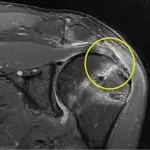

📌 2만례 이상의 어깨, 무릎 수술 경험

📌 <어깨통증 완치설명서> 저서 베스트셀러 선정